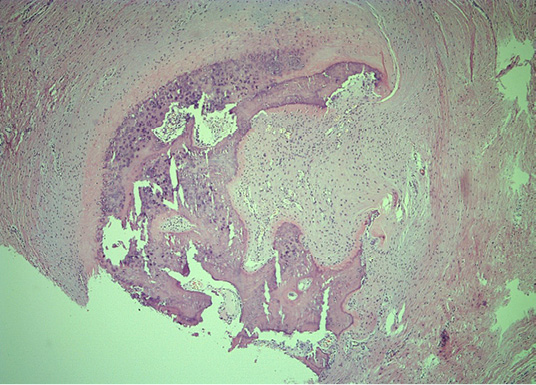

Microscopically, mature cortical and trabecular bone can be seen on the samples taken. The bone trabeculae are thin and widely separated, and between them is bone marrow, built of mature adipose tissue with multifocal hematopoietic activity. Peripherally, the cortical bone is adjoined by collagenous connective tissue and mature adipose tissue, with and easily expressed lymphocytic inflammatory infiltrate with perivascular distribution. In one part of the surrounding connective tissue, the process of forming new bone tissue, represented by primary bone tissue, can be seen (Figures 4–7).

Figure 6. Histologic section of the HO showing mature bone tissue and bone marrow with fat cells and haematopoiesis (He&Eo staining. Magnification ×40)

Figure 7. Representative peripheral area, demonstrating woven bone and compressed fibrous pseudocapsule on the lesions’ exterior (He&Eo staining. Magnification ×40)